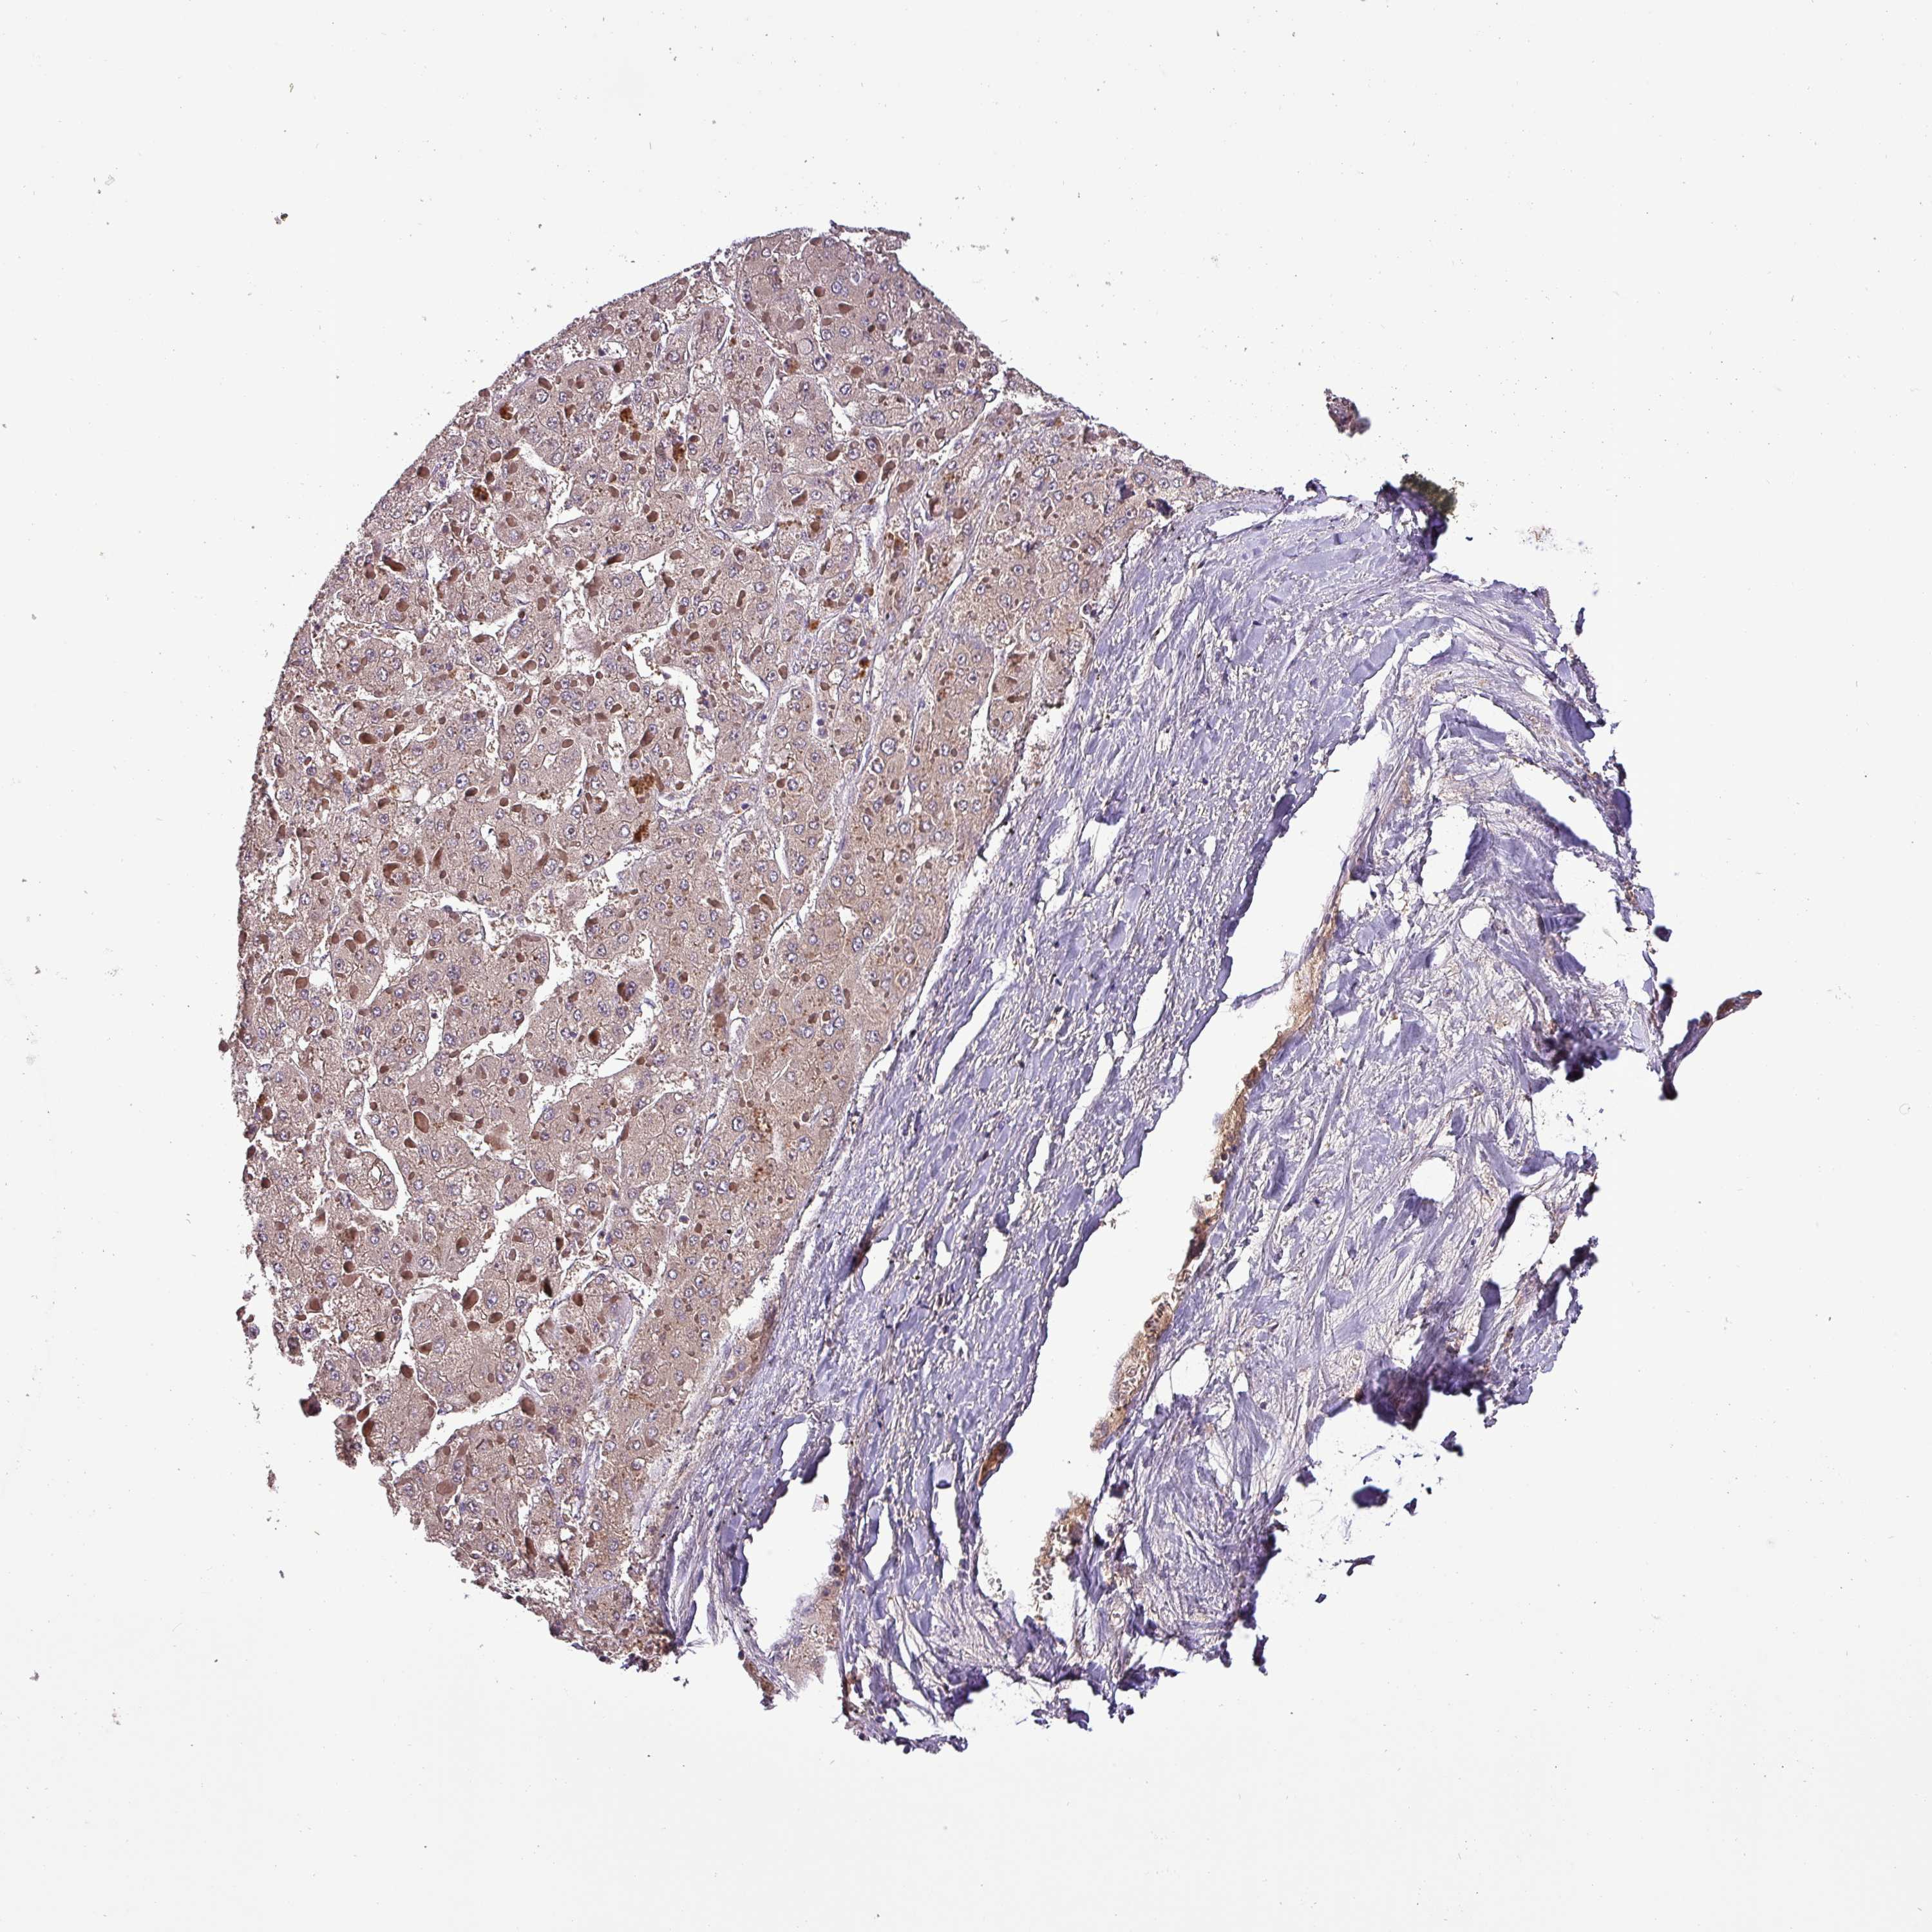

LIVER CANCER - Protein expressioni

A mouse-over function shows sample information and annotation data. Click on an image to view it in a full screen mode. Samples can be filtered based on level of antibody staining by selecting one or several of the following categories: high, medium, low and not detected. The assay and annotation is described here.

Note that samples used for immunohistochemistry by the Human Protein Atlas do not correspond to samples in the TCGA dataset.

Antibody stainingi

Antibody staining in the annotated cell types in the current human tissue is reported as not detected, low, medium, or high, based on conventional immunohistochemistry profiling in selected tissues. This score is based on the combination of the staining intensity and fraction of stained cells.

Each image is clickable and will lead to virtual microscopy that enables deeper exploration of all samples and also displays staining intensity scores, fraction scores and subcellular localization as well as patient and tissue information for each sample.

Antibody HPA051836

Staining

High

Medium

Low

Not detected

Intensity

Strong

Moderate

Weak

Negative

Quantity

>75%

75%-25%

<25%

None

Location

Nuclear

Cytoplasmic/membranous

Cytoplasmic/membranous,nuclear

Carcinoma, Hepatocellular, NOS